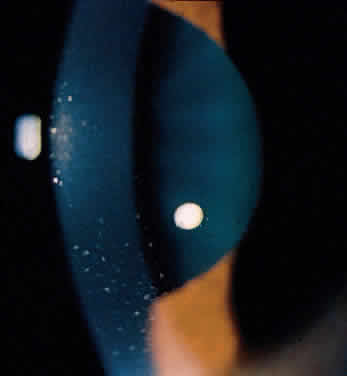

Ankylosing spondylitis is distinctly different from rheumatoid arthritis, although earlier literature did not make this distinction. The sacroiliac joint is usually the most easily visible area of involvement and is best seen in oblique views on radiography of the sacroiliac joint as periarticular sclerosis and irregular loss of the joint space. These patients are seronegative for rheumatoid factor and may have an elevated erythrocyte sedimentation rate.3,6 The presence of HLA-B27 antigen in 90% to 95% of white patients and 50% of black patients with ankylosing spondylitis is well documented, and the genetic predisposition to this disease has been recognized for many years. The relationship, however, is still incompletely understood at this point. HLA-B27 antigen is present in 6% to 14% of the white American population and 3% to 4% of the black American population. It is clear that people with this HLA type are at greater risk of developing one of the spondyloarthropathies, particularly ankylosing spondylitis, but as yet poorly defined environmental factors must be involved in triggering the development of the disease process.3,8 The development of acute iridocyclitis is even more strongly correlated with HLA-B27 antigen than is its association with joint changes. Of patients with HLA-B27 antigen, 20% to 25% will develop symptoms or radiographic evidence of spondylitis at some time in their life, and milder forms of the disease are commonly not diagnosed but believed to be due to back “strain” or injury. The incidence of clinical spondylitis is about equal between men and women, but the disease tends to be milder and more difficult to diagnose in women; its prevalence appears to approach 2% in those in the North American population who are HLA-B27 positive and who have been studied. The mechanism of how HLA-B27 antigen is involved in this disease process is unclear. HLA determinants are located on chromosome 6. These determine cell surface markers that enable the immune system to recognize each cell as self. One theory that has been advanced suggests that the HLA-B27 antigen may be similar to antigens of the cell wall of certain exogenous agents or may be changed by the agents in a manner whereby the immune system has difficulty recognizing or responding appropriately to the agent or the altered HLA-B27 antigen. In one study, patients with ankylosing spondylitis had lower in vitro responsiveness of lymphocytes to Klebsiella antigens than HLA-B27-positive and HLA-B27-negative controls.9 Antisera to certain isolates of Klebsiella lysed the lymphocytes of HLA-B27-positive patients with ankylosing spondylitis, but not the lymphocytes of HLA-B27-positive or HLA-B27-negative controls. This suggests that perhaps some Klebsiella antigens cross-react with a gene product closely associated with HLA-B27 or a Klebsiella-modified B27 antigen in patients with ankylosing spondylitis. Cross-reacting antigens have been identified in HLA-B27 and Klebsiella, Shigella, and Yersinia.10 The role of Klebsiella has not been clarified, and no other agent has been substantiated with respect to ankylosing spondylitis. Chlamydia has been suggested in some cases of Reiter's syndrome, especially in instances of nonspecific urethritis.11–13 Shigella, Salmonella, and Yersinia have been involved in clinical epidemics of postinfectious arthropathies.14 Additional theories involve HLA-B27 linkage with a specific immune response gene that predisposes patients to the disease, perhaps making them more susceptible to infection. The role of these factors remains to be clarified. The acute iridocyclitis associated with ankylosing spondylitis is characterized by rapid onset of pain, photophobia, and blurred vision. Conjunctival, episcleral, and scleral injection and edema are seen. Poorly defined keratic precipitates are seen in the lower half of the corneal endothelium, and the anterior chamber has heavy flare that may be uneven. If the process is severe, there may be clot formation in the pupil space.15,16 Cells in the anterior chamber may be so numerous that hypopyon will occur. Glaucoma can result from anterior chamber reaction blockage of the angle in the acute phase of inflammation and from pupil block from synechiae. Synechiae form early and, if not broken, will form lasting adhesions. Mydriatic and cycloplegic therapy is needed early in treatment. Spillover of inflammatory cells and inflammatory debris into the vitreous may occur, and the presence of disc blurring and macular edema is sometimes observed. This is sometimes also associated with hypotony. Posterior subcapsular cataracts and diffuse lens clouding are seen with severe prolonged episodes and repeated acute recurrences.15,16 The typical episode lasts from 2 to 6 weeks. Aggressive suppression of the inflammatory reaction with topical corticosteroids is usually sufficient and reduces tissue damage, if an early intensive schedule is used, rather than increasing the drop schedule as the reaction increases. These patients may need to be seen daily when they are acutely active and may need to be seen every 2 to 3 days until the process is stable or clearly resolving. Treatment must be continued for several weeks as the process is resolving or reactivation will occur. Oral corticosteroids can be given for short periods of time. Some patients experience elevation of intraocular pressure with corticosteroid therapy, particularly as the eye improves and the ciliary body is again more able to produce aqueous humor. The long-acting effects of periocluar injection of corticosteroids may become a more serious problem with persistent corticosteroid-induced glaucoma than the episode of acute iridocyclitis that was being treated. Frequent episodes of recurrent iridocyclitis may cause significant disability that results in loss of work, discomfort, and structural damage to the eye. These patients may benefit from longer term treatment with oral nonsteroidal anti-inflammatory agents, such as indomethacin or naproxen. These medications may help to reduce the severity and frequency of recurrences, but the pain-decreasing effects of these medications may make it more difficult for the patient to recognize an acute recurrence of the iridocyclitis. Patients should be examined for exacerbations of the inflammation if they note any change in vision, even minor symptoms. REITER'S SYNDROME OR POSTINFECTIOUS REACTIVE ARTHRITIS Reiter's syndrome is a clinical syndrome usually described as arthritis, conjunctivitis, or iridocyclitis and nonbacterial urethritis or cervicitis. A better definition may be needed, because not only may these not all be present, but also dysentery and mucocutaneous disease with balanitis, oral ulceration, or keratoderma blennorrhagicum may be part of the clinical picture. Enthesopathy of the plantar fascia or Achilles tendon is also suggestive of Reiter's syndrome. It is more commonly identified in males, but may be more frequent in females than previously thought.14 The incidence reported by Noer17 in US Navy personnel over a 10-year period was 4 in 100,000 men per year. HLA-B27-positive persons have approximately a 25% risk for Reiter's syndrome development after Shigella infection.18 Although the cause is unknown, the high correlation with the presence of HLA-B27 (75%)19 is clearly recognized. The previous discussion in the section on spondyloarthropathies concerning this HLA-B27 association demonstrates a genetic predisposition in a high percentage of these patients. In Reiter's syndrome, infectious agents are suggested by reports of clinically indistinguishable acute disease after epidemic dysentery and sexually transmitted nongonococcal urethritis thought to be due to Chlamydia20 or possibly Mycoplasma (Ureaplasma urealyticum).21,22 Large epidemics of dysentery have been linked to multiple occurrences of arthritis, urethritis, and iridocyclitis.17,23 Shigella, Campylobacter, Salmonella, and Yersinia have all been implicated.24 Microbial antigens have been identified in the synovium after infectious with Chlamydia, Yersinia, and Salmonella.25–27 Salmonella typhimurium is a frequently associated Salmonella pathogen causing reactive arthritis. This seronegative arthritis usually involves larger joints and the weight-bearing joints of the lower extremities. The knees and ankles are most frequently involved, with redness and diffuse swelling. Multiple joint involvement is usual. Periostitis and tendinitis may occur, especially involving the Achilles tendon, producing heel pain. Sacroiliac radiographic changes are present in up to 32% of patients.14 Children may be affected rarely.28 Reiter's syndrome tends to affect young adults in the range of 16 to 40 years of age. The diagnosis is sometimes hard to establish because the urethritis or cervicitis may be forgotten or suppressed and the enteritis and other symptoms may have been mild or not identified as abnormal. If a urethritis or cervicitis is present, cultures should be considered to make sure no treatable organism is present, such as gonococcus. Serologic testing for syphilis will help to rule out this sometimes-associated venereal problem. Low back pain due to insertional tendinitis and sacroiliitis is common. The dermal lesions typified by keratoderma blennorrhagicum, described as a hyperkeratotic erythematous dermatitis resembling pustular psoriasis, may not be present until later in the disease. It usually involves the hands and feet but may involve other areas. Superficial ulcers of the mucous membranes are frequent.29 Enteritis is usually a prolonged diarrheal episode with frequent passage of bloody, loose stools, but it may be a 24-hour episode of increased bowel activity.29 The conjunctivitis is usually described as mucopurulent and may be sterile. It may be accompanied by an iridocyclitis, episcleritis, or scleritis. Punctate and subepithelial corneal involvement has been reported. The iridocyclitis may be the presenting ocular manifestation. Recurrences are usually associated with an acute iridocyclitis, which is of rapid onset with conjunctival and episcleral edema and injection. The corneal endothelium has cellular debris and poorly defined, small-sized to medium-sized keratic precipitates.30 Heavy flare and cells and a very early tendency toward formation of posterior synechiae is characteristic, more so than in most other forms of acute iridocyclitis (Figs. 1, 2, and 3). Even the most aggressive pupil dilation management is sometimes inadequate for preventing synechiae. A peripheral iridectomy may be necessary to prevent iris bombé and angle closure if the synechiae cannot be broken enough to establish an opening for aqueous through the pupil (Fig. 4). The heavy flare is sometimes so plasmoid that cells are immobile and a fibrinlike clot may be seen in the pupil opening as the inflammation resolves. Cells and inflammatory debris may be seen in the vitreous, and blurring of the disc margins and macular edema may occur with severe or prolonged episodes. Lens clouding and posterior subcapsular cataracts occur with prolonged or repeated episodes. Hypotony can occur after a severe or prolonged course and may persist after resolution. Occasionally, secondary glaucoma may occur, owing to the anterior chamber reaction, in which case it will resolve as the inflammation resolves. With repeated recurrences, damage to the trabecular meshwork may occur, and prolonged recalcitrant glaucoma may result that may be poorly responsive to any medical or surgical management. This can be a serious factor in permanent visual loss with this type of iridocyclitis.15,16,30,31

Ocular inflammatory changes include conjunctivitis, episcleritis, keratitis, acute and chronic iridocyclitis, and posterior changes as well.38–43 The acute iridocyclitis is milder and frequently not accompanied by as much pain, photophobia, and redness as in the acute iridocyclitis associated with other spondyloarthropathies. Mild injection of the conjunctival and episcleral vessels and blurred vision may be the only symptoms of an acute flare of activity. The endothelium of the cornea usually has cellular debris and poorly formed keratic precipitates in the lower cornea. The anterior chamber contains cells and moderate flare, and a protein clot is not infrequent in the pupil, with early formation of posterior synechiae (Fig. 6); however, the synechiae are usually more easily broken than in ankylosing spondylitis and Reiter's syndrome.44 Treatment with topical corticosteroids and mydriatics is usually effective. The activity of the iridocyclitis has been reported to follow the activity course of the inflammatory bowel disease. Systemic treatment of inflammatory bowel disease has been noted to help the ocular inflammation. Decreasing the systemic treatment occasionally allows ocular inflammation to become visible and requires close observation and appropriate increase in local therapy.39,44–46 Surgical resection of inflamed bowel for other medical reasons has sometimes been reported to coincide with lessening of ocular inflammation,44,46 but these observations need better evaluation.42 Posterior segment manifestations, including retinal and choroidal vascular disease, are also sometimes noted.47,48